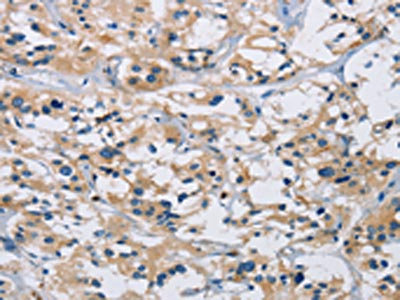

The image on the left is immunohistochemistry of paraffin-embedded Human gastic cancer tissue using CSB-PA121041(IL17RB Antibody) at dilution 1/40, on the right is treated with synthetic peptide. (Original magnification: ×200)

The image on the left is immunohistochemistry of paraffin-embedded Human thyroid cancer tissue using CSB-PA121041(IL17RB Antibody) at dilution 1/40, on the right is treated with synthetic peptide. (Original magnification: ×200)